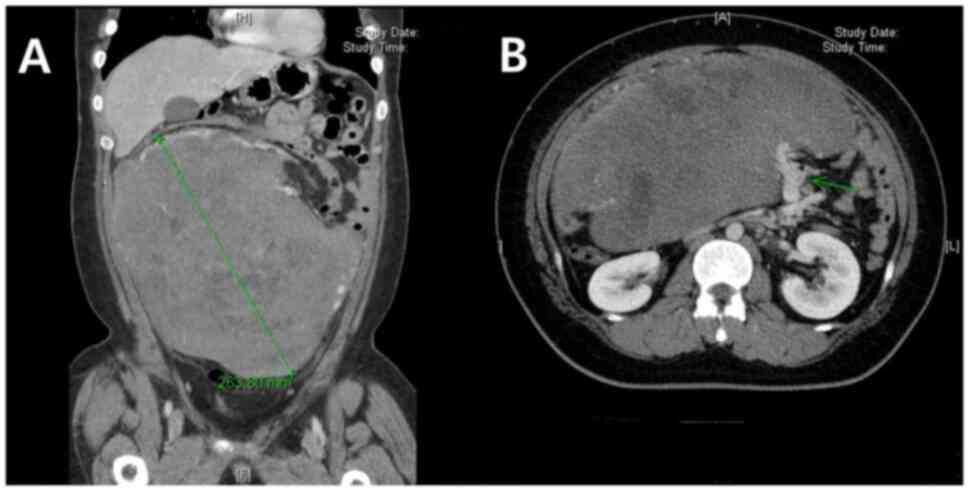

A giant, rapidly growing intra‑abdominal desmoid tumor of mesenteric origin in an adolescent male: A case report and literature review

A desmoid tumor is a fibroblastic proliferation of mesenchymal origin, which has no metastasizing potential but is locally aggressive. Although treatment has shifted to observation and active surveillance for newly diagnosed patients with desmoid tumors, intra‑abdominal mesenteric tumors or tumors that persistently grow and provoke symptoms may need prompt surgical treatment. There have only been a small number of case reports that illustrate large sporadic intra‑abdominal mesentery‑deriving desmoid tumors in which the longest diameter was ≥19 cm. In the present study, an adolescent male patient with a rapidly growing 38‑cm long sporadic intra‑abdominal desmoid tumor of mesenchymal origin is reported. The patient was treated with chemotherapy followed by surgical resection due to non‑responsiveness and progression of symptoms, then with maintenance adjuvant chemotherapy to prevent recurrence due to the large size of the tumor. Despite the rapid growth of the tumor and its high occupancy in the intra‑abdominal cavity, an R0 resection was successful with organ preservation. The patient has been recurrence‑free for 2 years, and further follow‑up is expected in the future.